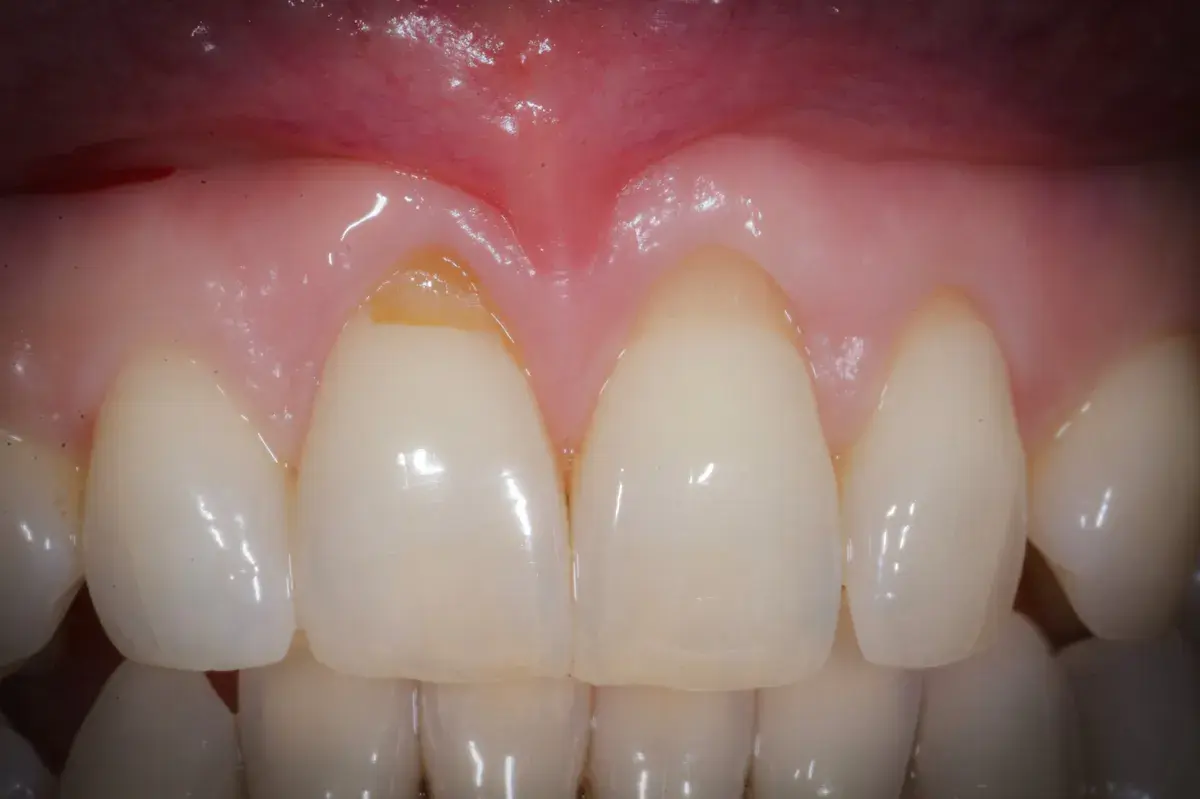

Perché le gengive si ritirano, quando preoccuparsi e cosa può fare il parodontologo. Classificazione di Cairo, innesto connettivale, lembo coronale.

Innesto connettivale per recessioni gengivali: tecnica gold standard per ricostruire la gengiva e proteggere i denti esposti.

Le recessioni gengivali possono essere corrette o meno. Esistono indicazioni assolute e relative al trattamento chirurgico con copertura radicolare.